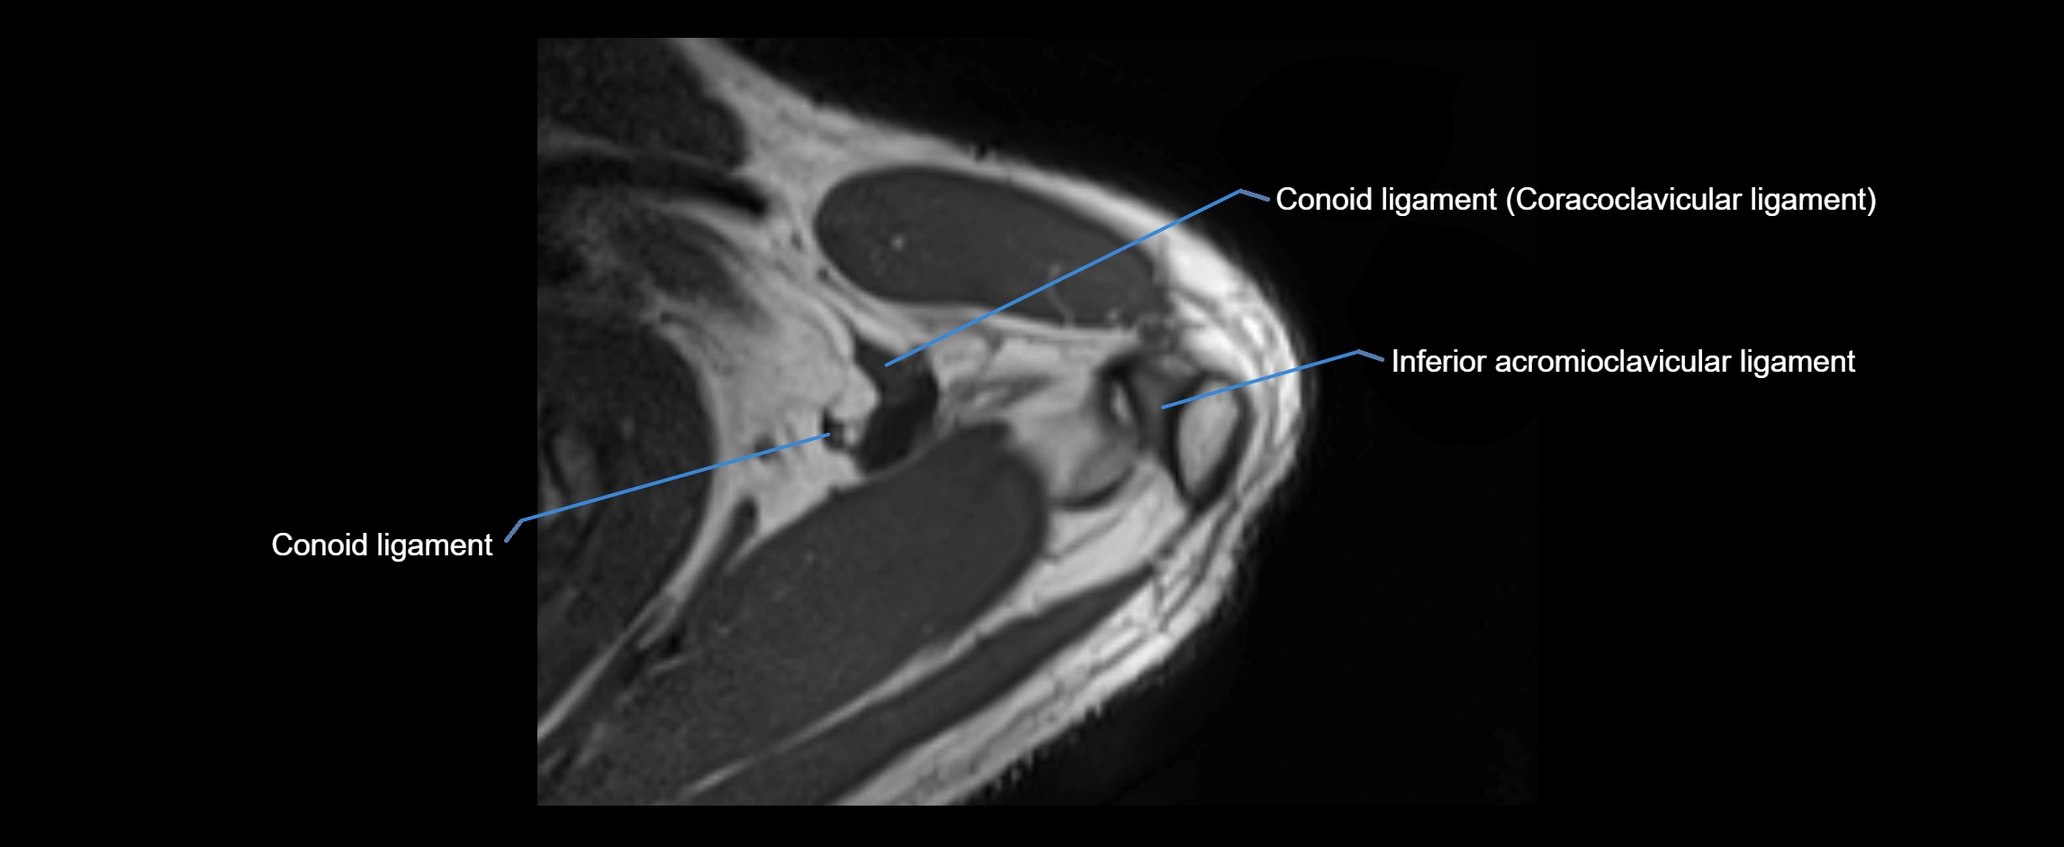

CT image

image

CT Appearance

Non-Contrast CT:

• Ligament: Not directly visualized due to small size and low density.

• Bony landmarks: Lateral clavicle and acromion clearly seen; cortical margins well defined.

• Pathology: Detects fractures, joint subluxation, osteophytes, and degenerative changes.

• Alignment assessment: Evaluates AC joint spacing and clavicular displacement.